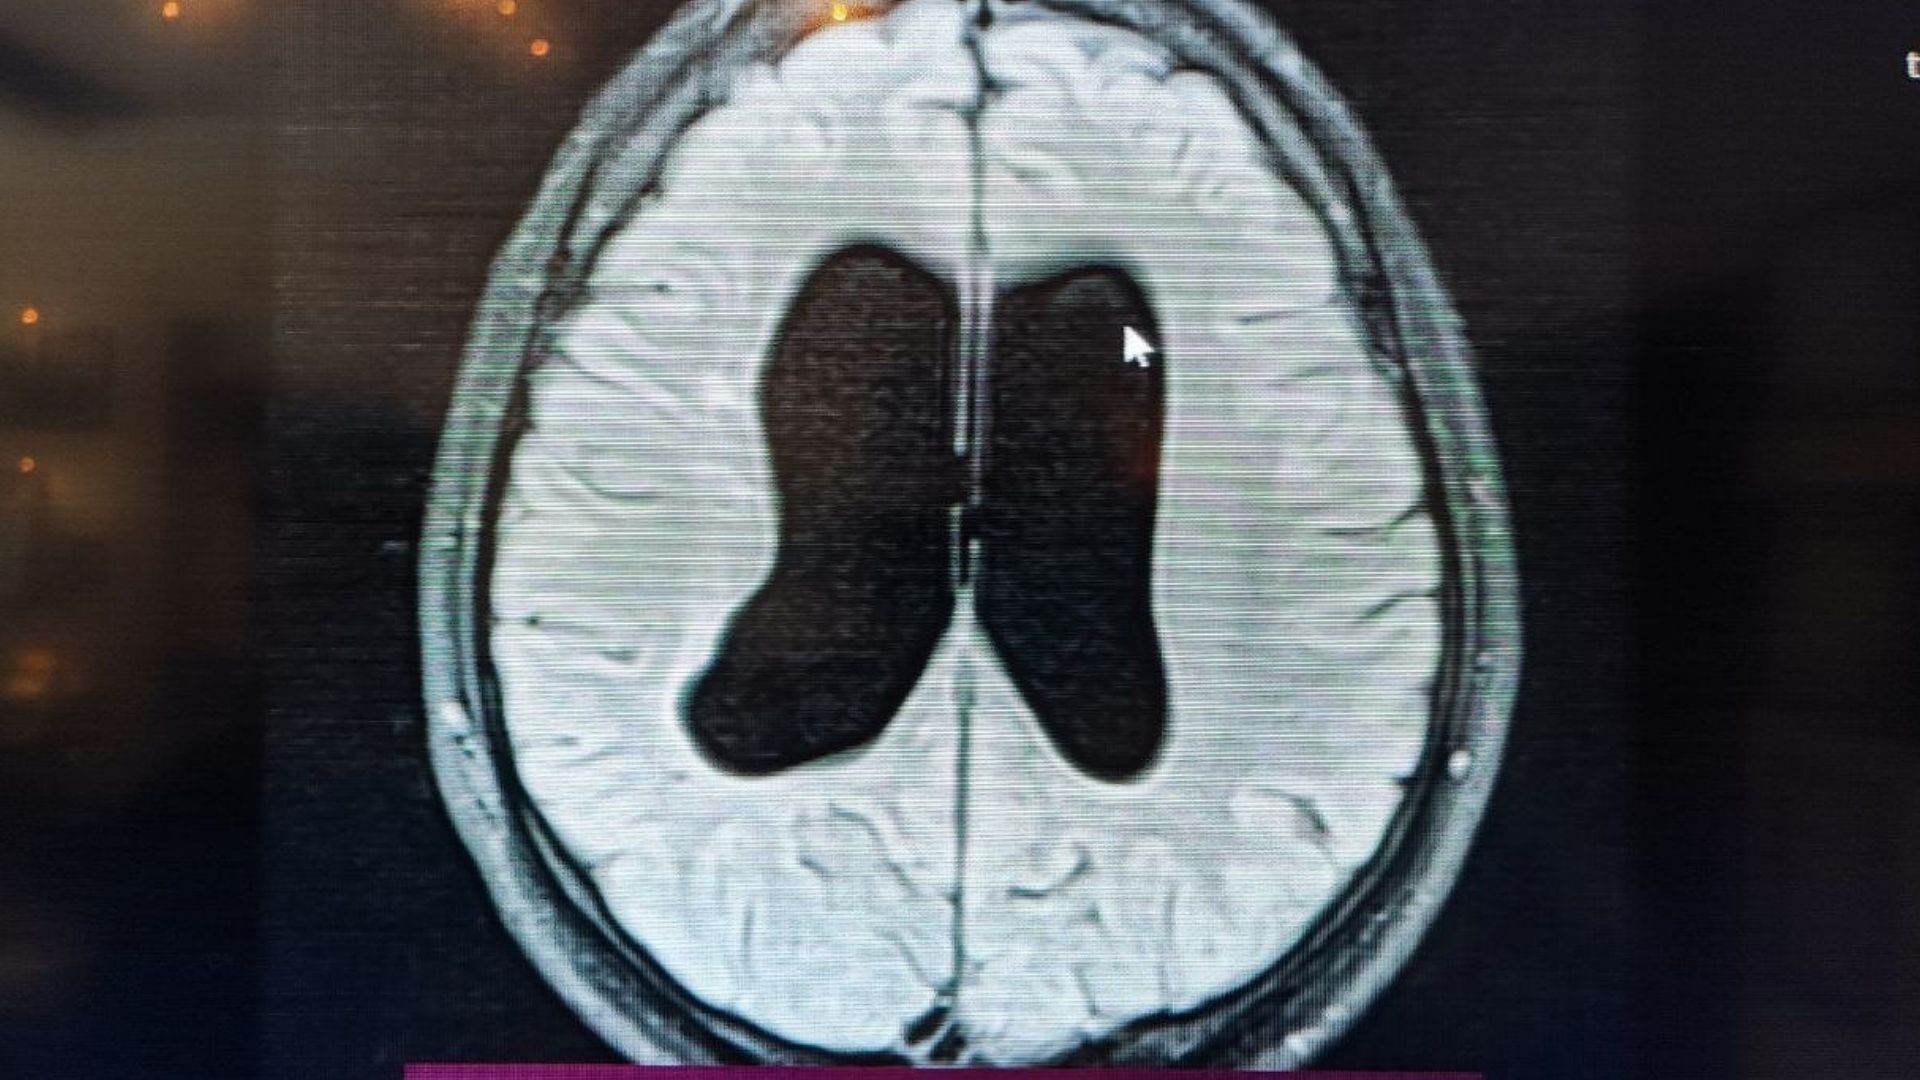

“Doğar doğmaz hidrosefali tanısı konulmuş, acil ameliyat önerilmiş. Ancak muayenede bıngıldak normal seviyedeydi. Anneye kusma durumunu sordum; yalnızca yemek sırasında olduğunu öğrendim. Klinikteki bulgular görüntüleme ile uyumlu değildi. Bu nedenle ‘acil ameliyat gerekmiyor’ dedim. İzlemeyi tercih ettik. Sadece bıngıldakta bombe artışı ve tekrarlayan kusma olursa müdahale edeceğimizi söyledik.”

Prof. Dr. Şen, bebeğin durumunun anne karnındaki süreçten kaynaklandığını ve beyne ek bir baskı yapmadığını belirterek, “Bu bir arrest hidrosefaliydi. Bazı çocuklarda ameliyat yerine izlem çok daha doğru yaklaşımdır” ifadelerini kullandı.